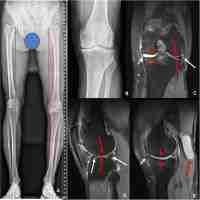

| Abstract | Background The purpose of this study was to evaluate the efficacy of arthroscopic knee cavity internal drainage and cyst cavity debridement operation of popliteal cyst in knee osteoarthritis patients. Methods From August 2007 to March 2013, 58 knee osteoarthritis patients with popliteal cyst were treated with arthroscopic knee cavity internal drainage through posteromedial portal and popliteal cyst cavity debridement through superior posteromedial portal. In all patients, preoperative magnetic resonance imaging (MRI) was performed to detect combined intra-articular pathology and the communication between popliteal cyst and knee cavity. Clinical efficacy was evaluated through VAS score and Lysholm score. Results All patients had neither recurrence of popliteal cyst nor complaints of pain, swelling, or functional impairment at average 24 months follow-up after surgery. Postoperatively, VAS score was decreased significantly and Lysholm score was raised significantly comparing preoperatively. Conclusion Arthroscopic knee cavity internal drainage operation through posteromedial portal and popliteal cyst cavity debridement through superior posteromedial portal is an effective minimally invasive surgery method for the treatment of popliteal cyst without recurrence in knee osteoarthritis patients. |